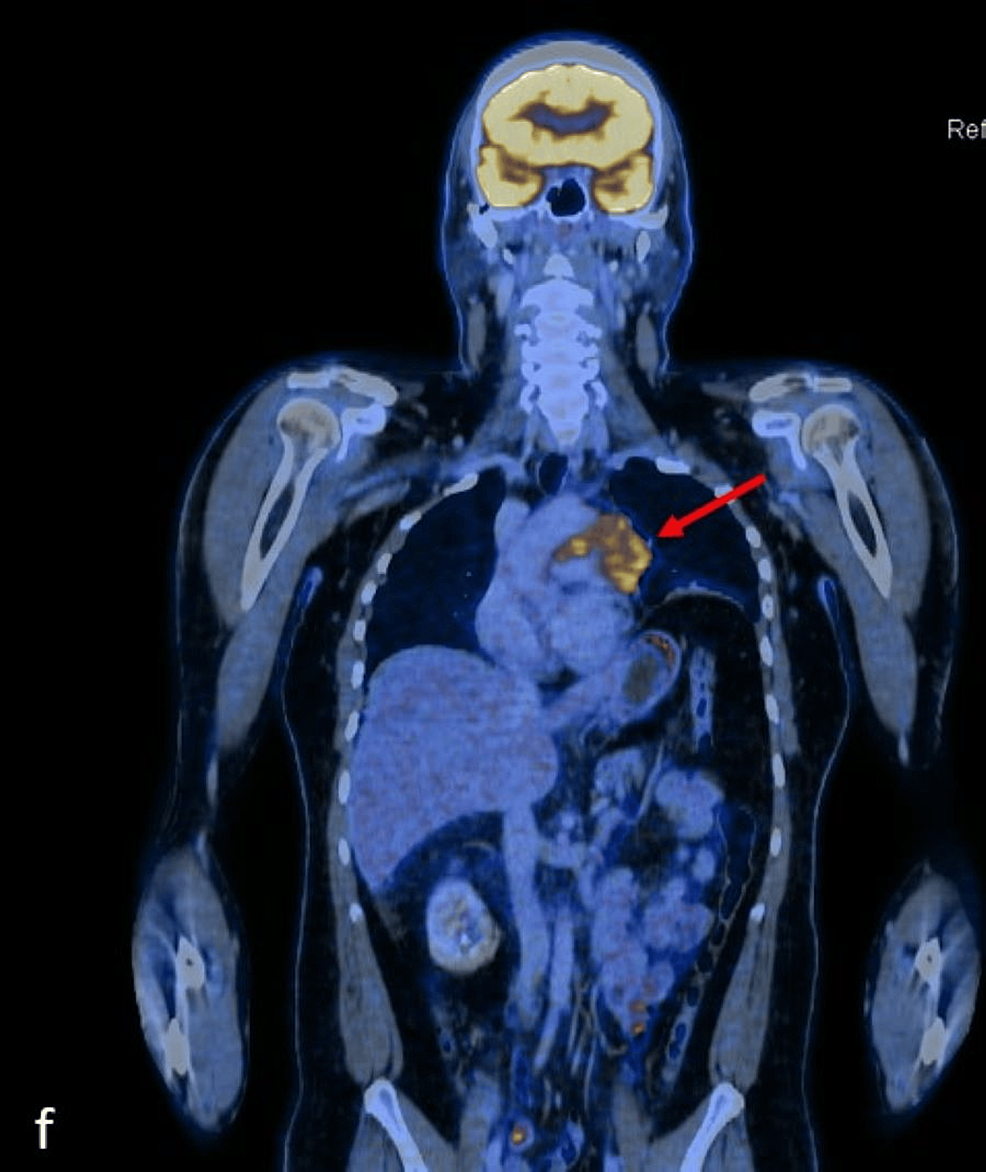

Cancers Free FullText Thymic Lymphoepithelial Carcinoma Associated Thymic Lymphoepithelial Carcinoma Thymic lymphoepithelial carcinoma (tlec) is a primary thymic carcinoma that accounts for about 14% of all thymic epithelial tumors and is classified into. In the who 2021 classification, thymic carcinoma includes the following new subtypes (): Thymic epithelial tumors (tets) are rare tumors, including thymoma, thymic carcinoma, and thymic neuroendocrine tumors. (1) micronodular thymic carcinoma with lymphoid hyperplasia (fig. The. Thymic Lymphoepithelial Carcinoma.

Figure 1 from Thymic Lymphoepithelial Carcinoma Associated with Epstein Thymic Lymphoepithelial Carcinoma (1) micronodular thymic carcinoma with lymphoid hyperplasia (fig. Thymic lymphoepithelial carcinoma (tlec) is a primary thymic carcinoma that accounts for about 14% of all thymic epithelial. Thymic epithelial tumors (tets) are rare tumors, including thymoma, thymic carcinoma, and thymic neuroendocrine tumors. In the who 2021 classification, thymic carcinoma includes the following new subtypes (): The recognition of clinical, radiologic, and.. Thymic Lymphoepithelial Carcinoma.

Cancers Free FullText Thymic Lymphoepithelial Carcinoma Associated Thymic Lymphoepithelial Carcinoma The recognition of clinical, radiologic, and. In the who 2021 classification, thymic carcinoma includes the following new subtypes (): Thymic lymphoepithelial carcinoma (tlec) is a primary thymic carcinoma that accounts for about 14% of all thymic epithelial tumors and is classified into. (1) micronodular thymic carcinoma with lymphoid hyperplasia (fig. Thymic lymphoepithelial carcinoma (tlec) is a primary thymic carcinoma that. Thymic Lymphoepithelial Carcinoma.